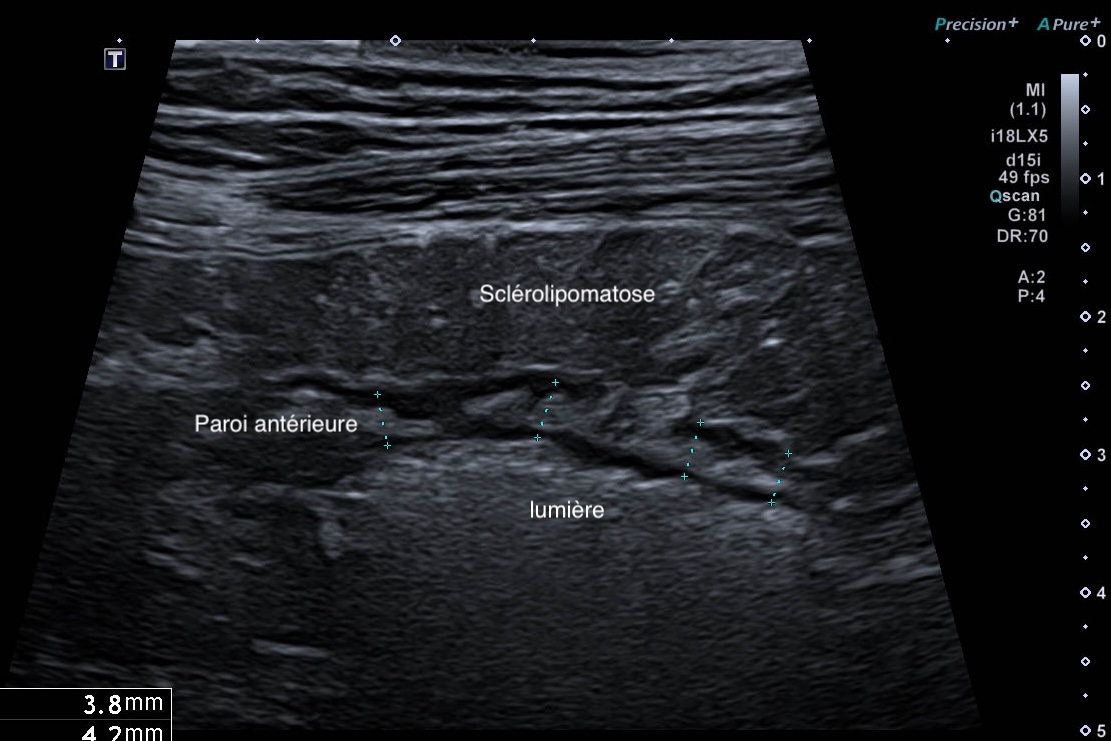

C'est la forme chronique de l'inflammation de la graisse, l'inflammation devient scléreuse, figée arrondie, plus hypoéchogène

- attraction de la séreuse en profondeur qui prend un aspect spiculé

- plus hypoéchogène

- Déformant la paroi localement

Sclérolipomatose antérieure iléon, graisse hypo échogène paroi Limberg 1 au maximum